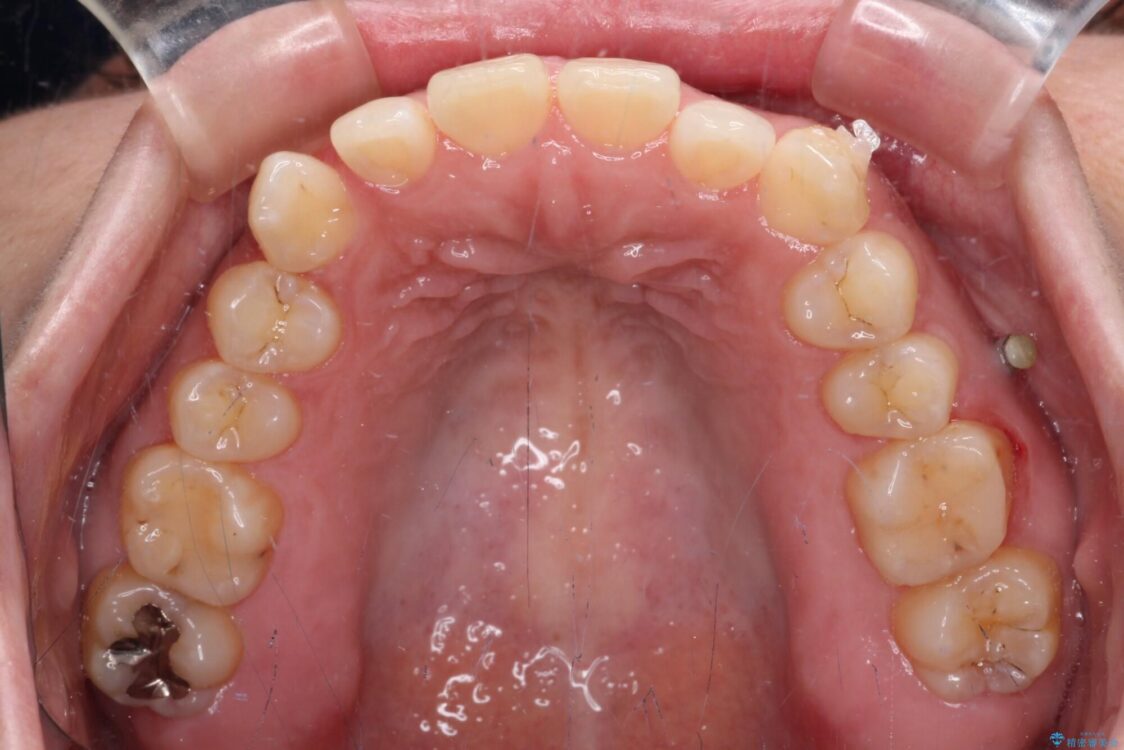

治療前

• 【モニター】カリエール・ディスタライザーを併用した八重歯のインビザライン矯正 治療前画像